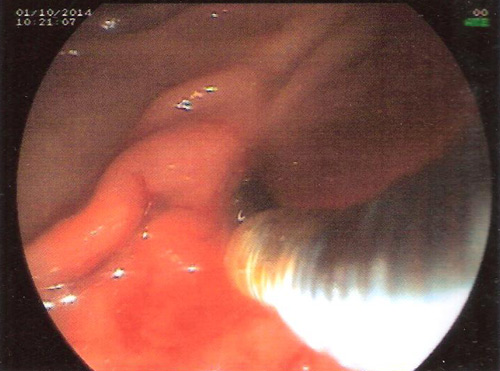

ERCP was performed.Selectuve cannulation was done of the pancreatic duct .The wire could negotiate the stricture in the neck but even a 5 Fr biliary dilator could not.A stent retriever was screwed over the wire and the stricture dilatation obtained with removal of fragments of stone.A pancreatic stent was placed .